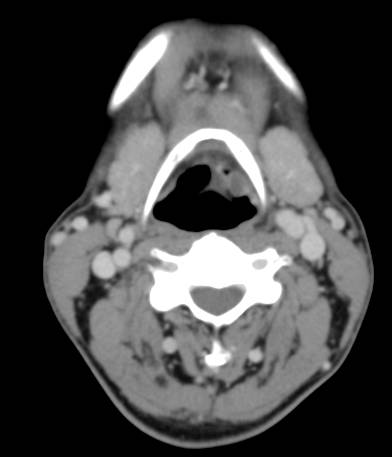

左侧会厌间隙见少许软组织密度影,增强可见环形强化,壁薄。双侧颈部未见明显肿大淋巴结。

(1)弥漫型,喉粘膜弥漫性、不对称肿胀增厚,以会杓皱襞、会厌、杓状区常见,喉结核关于喉旁间隙或会厌前间隙是否侵润,文献中有不同意见。(2)局灶性(肿块型),可见软组织肿块,密度欠均匀,增强可见环形强化。